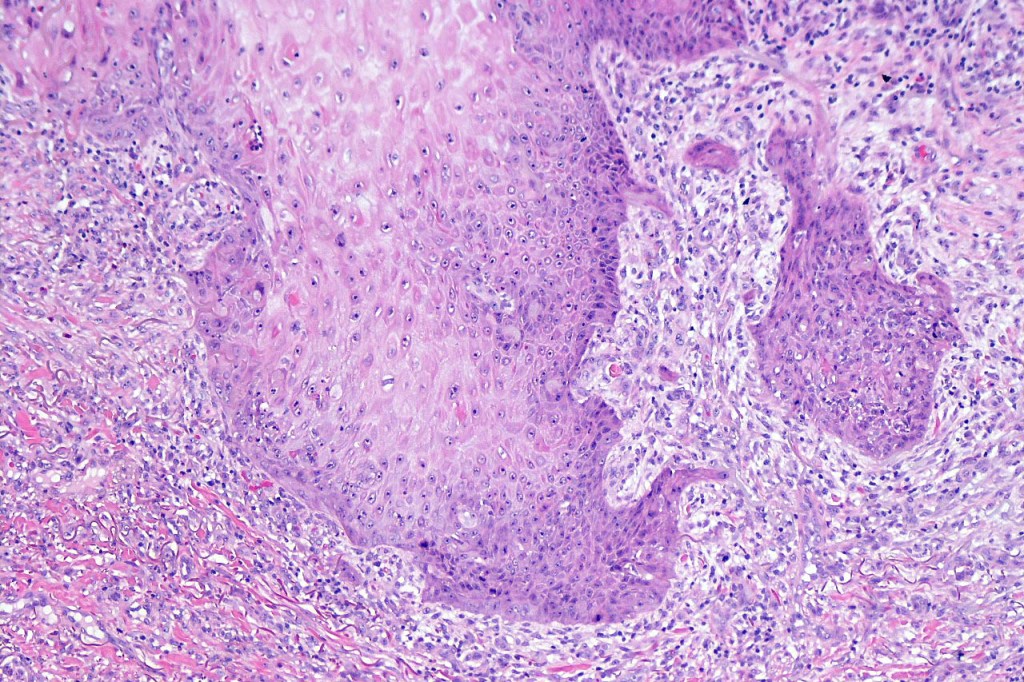

•Keratoacathoma (nowdays regarded as a variant of well differentiated squamous carcinoma) is characterized by a crateriform squamous epithelial lesion (dilated follicular infundibulum) with central keratin plug and adjacent collarette extending to the mid-dermis

•Well differentiated squamous epithelium often with a characteristic ground-glass appearance

•Only mild pleomorphism & basally located mitoses

Below is a fascinating case shared on McKee Derm by Dr. James Simpson. There is an obvious keratoacanthoma but at the edge of the lesion there is marked atypia with nuclear enlargement and pleomorphism. This is also evident in the adjacent epidermis and in the deeper nests.